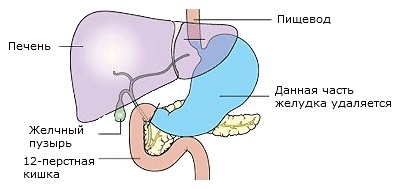

În cazul în care cancerul este localizat în mijlocul stomacului, poate fi necesar pentru a finaliza îndepărtarea organului. Această operație se numește gastrectomie totală (total) cu impunerea anastomoza Y-Roux. După o intervenție chirurgicală, esofag va fi conectat direct la intestinul subțire. cicatrice postoperatorie va fi amplasat vertical (de sus în jos) sau orizontal (transversal pe abdomen).

Diagrama arată anatomia stomacului înainte de operația de suprapunere în formă de Y anastomoza Roux